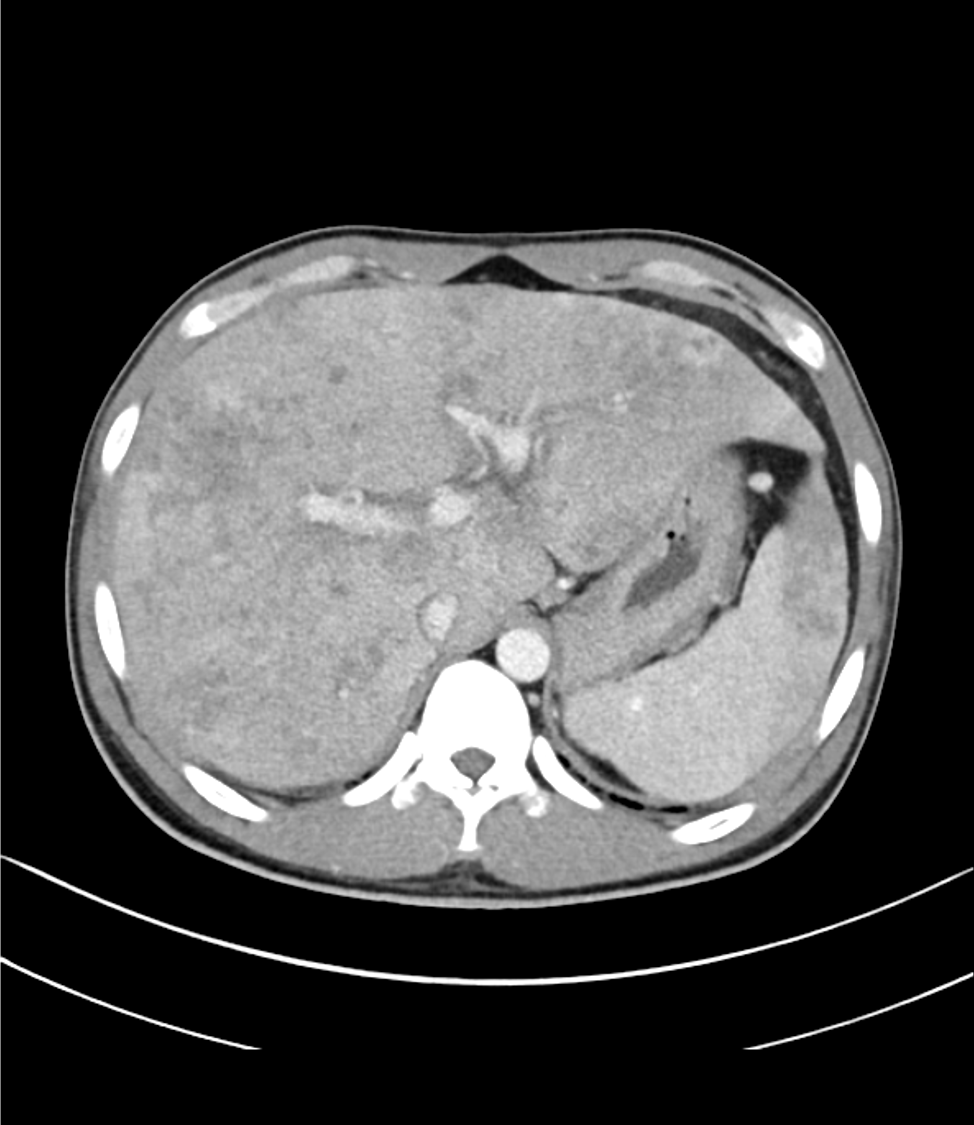

ライギョを加熱不十分で食べたエピソードと、発熱、好酸球増多があり、寄生虫感染が疑われ、精査目的にCTを撮像した。

肝内に地図状の乏血性の領域や、病変内に門脈枝の貫通像がみられ、これらは好酸球増多症における肝病変として矛盾しない所見であった。

好酸球増多症では、肝臓の好酸球浸潤や門脈域を中心とした限局性の壊死が見られる。これらを反映した所見を捉えるのには、ダイナミックCTを撮像することが望ましい。

動脈相では乏血性の領域が見られ、門脈相では最もコントラストが強まる。平衡相では遅延性濃染がみられる。本症例はこれらの所見に合致した。